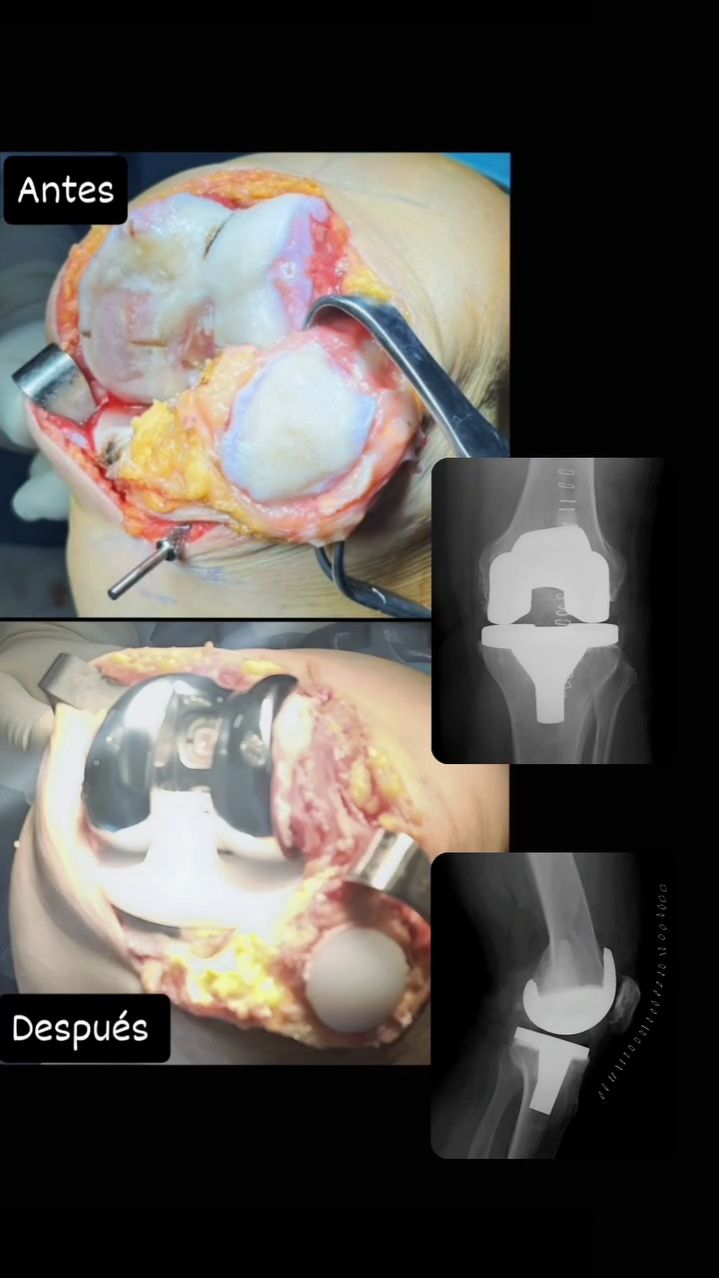

• Prótesis de Rodilla

Artroplastia rodilla con prótesis total Sin especificar